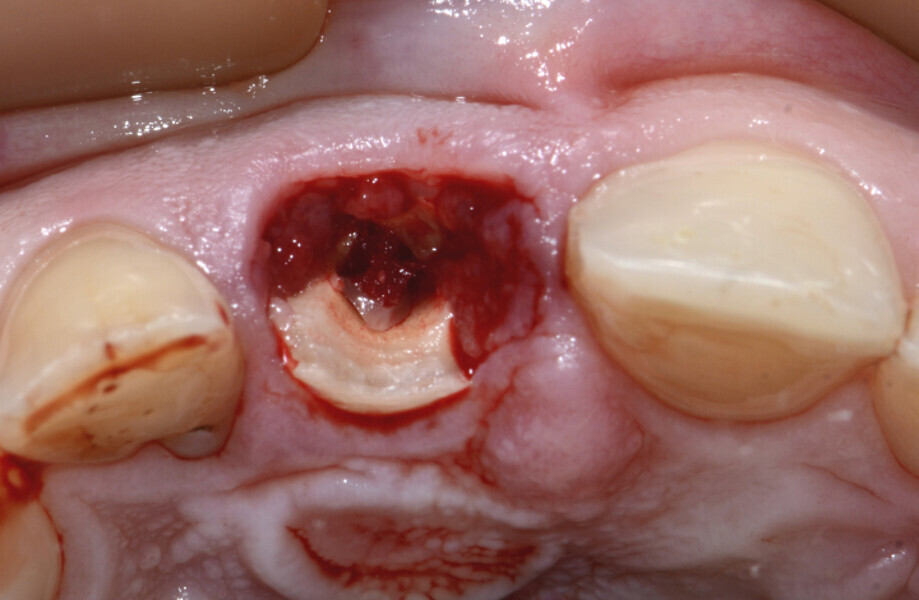

Fig. 9: Visible granulation tissue at the resorption and fracture area of tooth #11.

Fig. 10: Removal of the granulation tissue with an Er:YAG laser.